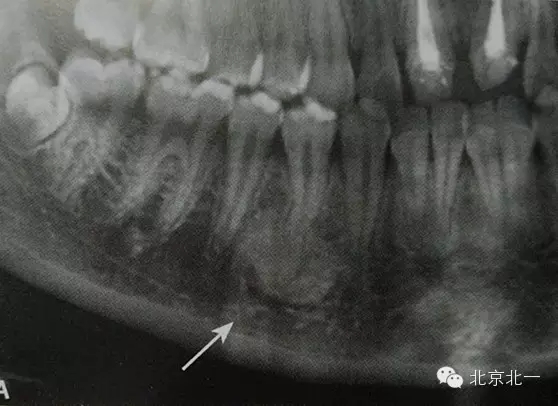

3)骨島:

概述:

主要和根尖型骨島鑒別,主要集中位于根尖區(qū)的骨島,

【CBCT表現(xiàn)】:

在CBCT上,根尖型骨島無低密度帶狀影包繞,與周圍骨質(zhì)分界清晰,具有特征性的毛刷樣邊緣,且其發(fā)生區(qū)域的牙根牙周膜影像連續(xù)、完整、不導致頜骨的膨隆。

右下頜C4根尖區(qū)課件一類圓形高密度影,與周圍骨質(zhì)分界清晰,C4牙周膜影像連續(xù)、完整,下頜骨未見膨隆。